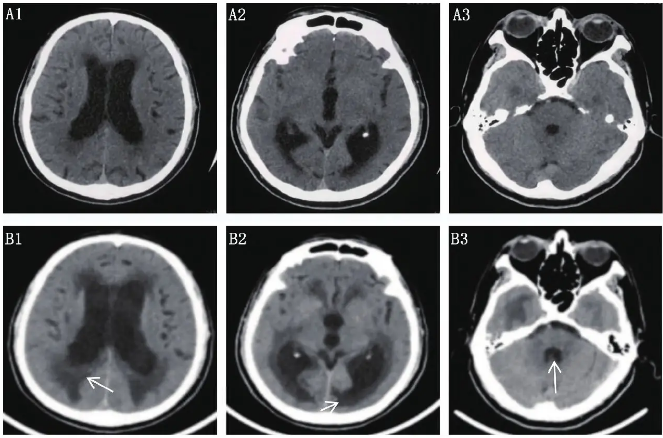

手术后颅骨缺损合并脑积水23例临床分析

病例

2025-10-02